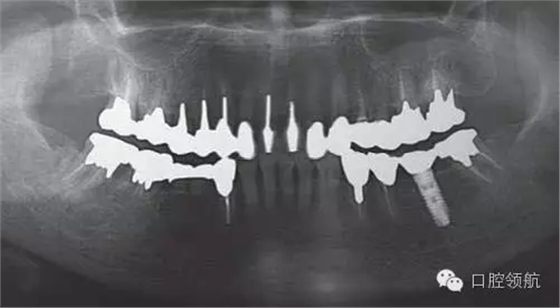

患者因為種植體出現(xiàn)松動來院就診。于外院接受的植入手術和修復,最近感覺到開始出現(xiàn)松動。在附近口腔醫(yī)院就診,被告之因“種植體本身松動”需到大學附屬醫(yī)院就診,然后來我院接受治療。初診時的口腔內所見, (右下第6顆牙) 修復體的松動以及周圍發(fā)紅的黏膜組織 (圖1)。(右下第6顆牙) 上部修復體咬合面金屬的露出,可能是為了防止上部修復體的旋轉,修復體和鄰牙用樹脂進行連接。從全景X線片上,可看到種植體和上部修復體之間有著細小的間隙(圖2)。

圖2 全景片顯示,種植體和上部修復體之間有著細小的間隙。

①全景或者X線牙片,通過影像觀察診斷上部修復體和種植體之間是否存在間隙,或種植體周圍是否能看到透射影像(圖2)。